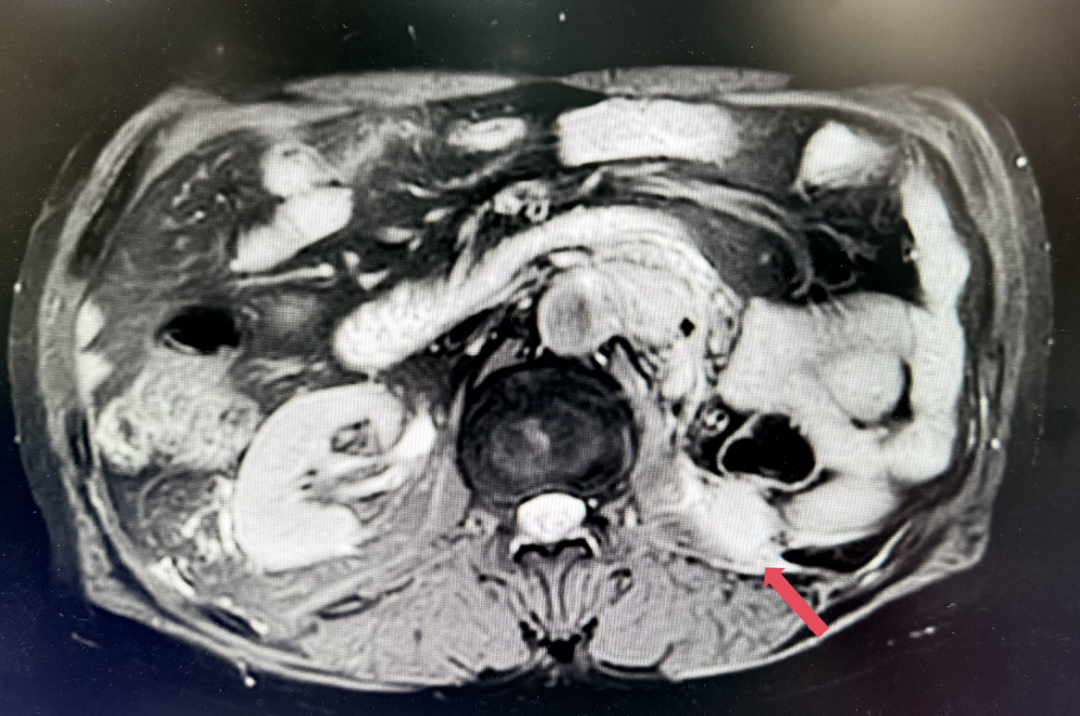

2023年11月:治疗10个月(C15)评估,肿瘤负荷减少至41mm,维持PR。

2025年1月:序贯为呋喹替尼单药(5mg,po,qd,D1-14,q3w)治疗。

2026年4月:持续维持PR,PFS超过37个月。

患者初诊时68岁,2020年9月因“体检发现左肾占位2年”行腹腔镜下左肾根治性切除术,术后病理提示为肾透明细胞癌,pT3aN0M0,未行术后辅助治疗、未规律复查。2022年3月胸腹盆CT示腹膜后转移,IMDC评分0分,低危组。随后予一线培唑帕尼治疗,最佳疗效SD,2022年11月PD。于2023年1月经筛选进入Ⅲ期FRUSICA-2临床研究,开始接受呋喹替尼联合信迪利单抗二线治疗,用药6周(C2)后首次肿评即实现疗效PR(缩瘤率40.2%),用药10个月时缩瘤率近七成(68%),并维持上述水平至今,PFS已经超过37个月,在二线治疗中实现了长期无进展生存。同时,患者对呋喹替尼联合信迪利单抗方案耐受性良好,仅见轻微蛋白尿和偶然腹泻,未见其他不良反应,也未见免疫治疗相关不良反应。该方案有望为TKI经治的晚期肾癌患者带来新的选择,为实现长期生存提供可能性。